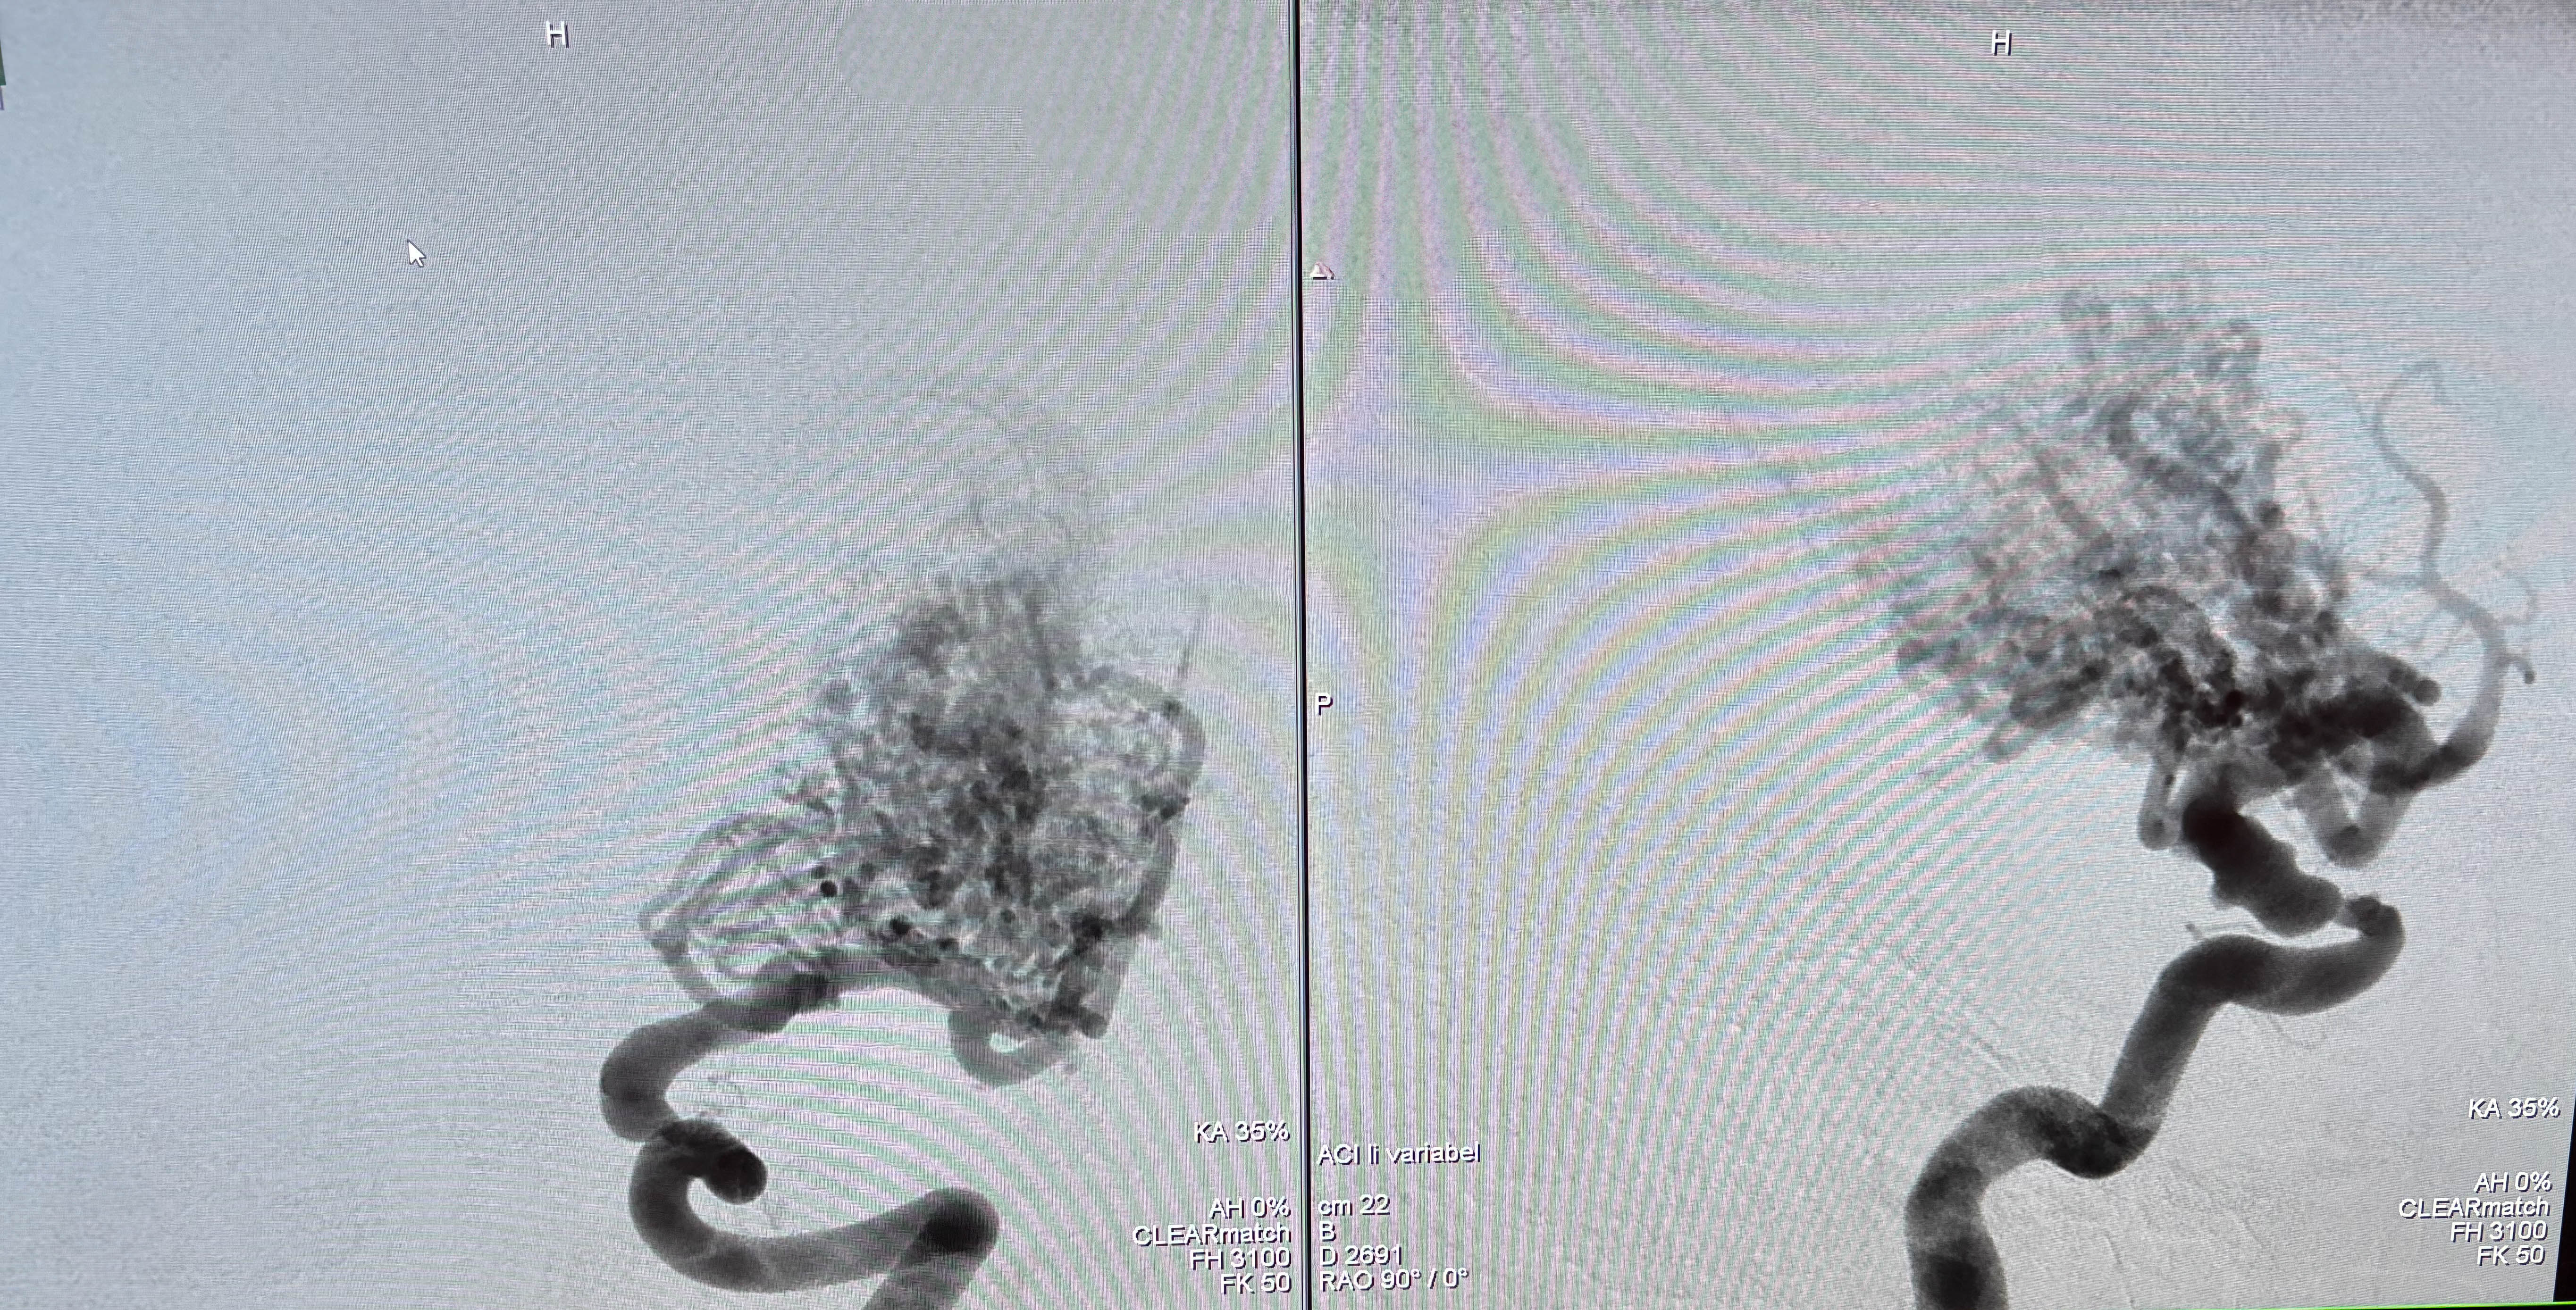

Gefäßfehlbildungen sind sehr komplexe Erkrankungen, die eine präzise und schonende Behandlung erfordern. Seit 2003 – damals mit Prim. em. Dr. Johannes Trenkler – bündeln Prof. Dr. Georges Rodesch vom Hopital Foch nahe Paris und Prim. Dr. Michael Sonnberger, Vorstand des Instituts für Neuroradiologie am KUK, ihre Expertise. Jedes Jahr werden am Neuromed Campus speziell ausgewählte Patientinnen und Patienten individuell betreut und mit der bewährten Embolisation therapiert.

Dabei werden krankhafte Blutgefäße gezielt verschlossen, um Symptome zu lindern und Komplikationen zu vermeiden. Dank der langjährigen gemeinsamen Arbeit ist die Embolisation heute eine sichere und effektive Behandlungsoption, die weltweit bekannt ist und die Lebensqualität unserer Patientinnen und Patienten deutlich verbessert.

Am Bild von links: Prof. Dr. Georges rodesch, Prim. em. Dr. Johannes Trenkler und Prim. Dr. Michael Sonnberger